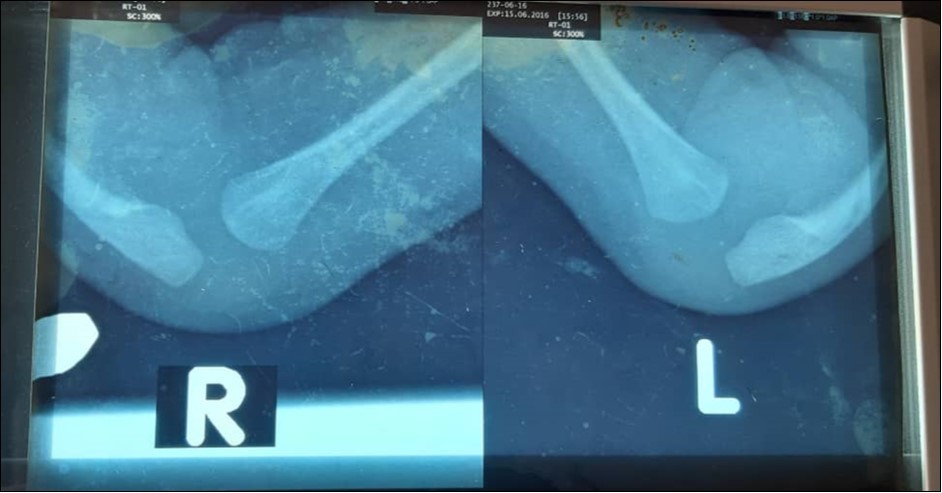

Physical examination revealed a young infant who was active. Both forearms were shortened and bowed ulnarwards. There was severe radial deviation at both wrists. There were no abnormalities detected in other systems. X-ray confirmed bilateral Bayne type IV deformity, Figure 1. Complete blood count was normal.

Figure 1.Depicts pre-operative radiographs of the forearms of the infant showing bilateral absence of the radius